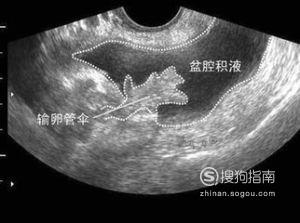

在备孕期间患上盆腔积液之后会担心盆腔积液会不会影响怀孕呢。下面就来跟小编一起了解了解吧,到底盆腔积液会影响怀孕呢?想要知道的人可以跟过来看看哟~

盆腔积液要看是什么原因造成的,生理性的盆腔积液多发生在妇女排卵后或早孕期,多可自然消失,这类的少量盆腔积液不影响怀孕,也不影响胎儿。

病理性的妇科盆腔积液多是盆腔炎附件炎或子宫内膜异位症引起的。在临床上大多数妇女的盆腔积液是由于炎症引起,是盆腔存在炎性渗出物,如果不加以治疗的话,可以慢慢长大。太大了,药物就不容易消除了,如果积极的对症治疗,盆腔积液会很快消失。盆腔积液消失后也不影响怀孕。

盆腔积液患者大多数具有腰痛、下腹痛(或两侧少腹痛)等症状,有些患者可有带下增多,多因盆腔炎症未能彻底治愈、病程迁延、炎症造成的浆液性渗出物积聚而形成积液(水)。也有少数因宫外孕破裂、黄体破裂、盆腔脓肿、巧克力囊肿、卵巢癌引起。积液多存在于子宫直肠凹陷处等盆腔内位置较低处,配合后穹窿穿刺或腹腔穿刺,可提高诊断率。中医认为其病机主要为经行、产后,胞脉空虚,邪毒乘虚内侵,湿浊、热毒蓄积胞中,与气血相搏。以致脏腑功能失调,冲任受损,日久则血瘀气滞,湿毒内蕴,聚湿成(痰)饮,而发为本病。病理因素主要为湿(饮)、热、毒、瘀。